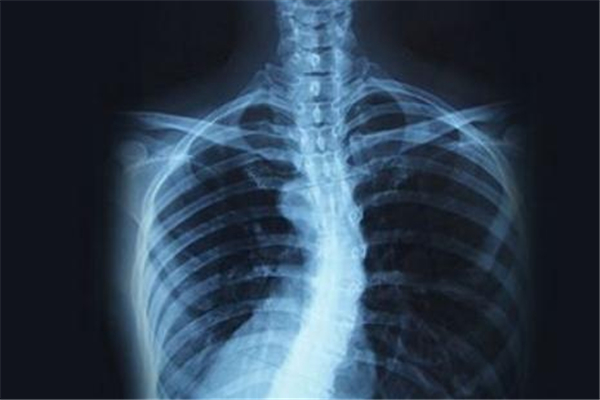

僵直性脊椎炎是一種病因不明,慢性的全身性發(fā)炎疾病,最主要是侵犯脊椎關(guān)節(jié)以及附近肌腱、韌帶等軟組織,影響到中軸骨及接骨點(diǎn)的肌腱或韌帶的慢性病,這種病會(huì)使身體脊椎鈣化僵硬,因?yàn)闀?huì)造成畸形、駝背,脊椎黏合后因喪失柔軟度,變得較易骨折或因而造成神經(jīng)壓迫,就像是脆弱的竹竿一樣無(wú)法順利彎曲,所以又被稱為竹竿病,同時(shí)也有家族遺傳的傾向。

它是一種不可逆的疾病,一旦發(fā)生就會(huì)持續(xù)惡化下去,從一開(kāi)始的下背痛,脊椎、髖骨、骨盆薦骨發(fā)炎,接下來(lái)出現(xiàn)骨點(diǎn)及關(guān)節(jié)鈣化、僵直的情形,然后再發(fā)生脊柱無(wú)法彎曲、失去彈性,到最終發(fā)炎及僵直的情況會(huì)向脊椎上下蔓延,這種發(fā)展實(shí)在是很嚴(yán)重,輕忽不得。